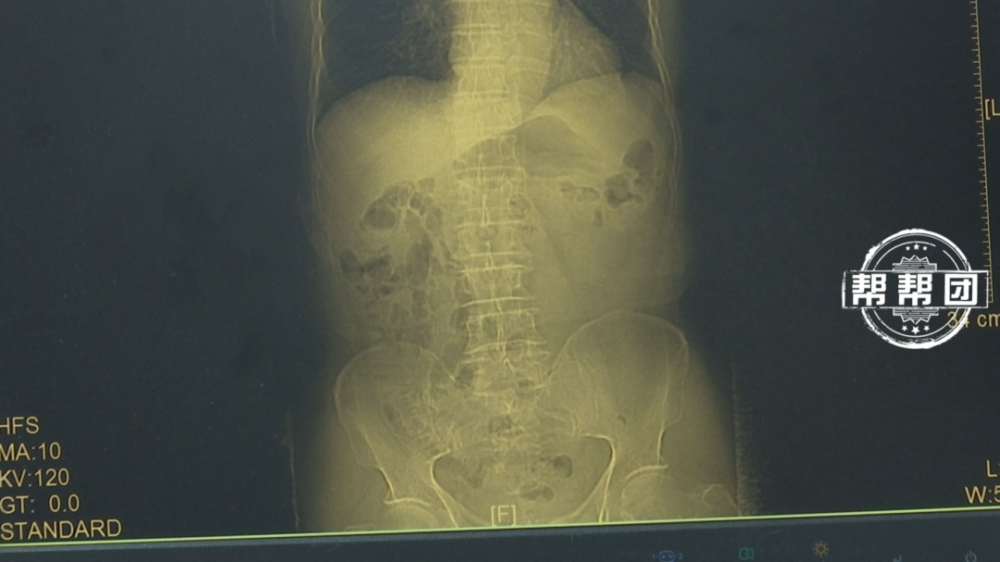

事情还要追溯到不久前,64岁的刘阿姨开始反复腹痛,前去福建协和医院就诊,被确诊为胃癌,刘阿姨惊吓之余也让丈夫做了检查,果然,65岁的刘叔叔也查出患有胃癌,两人癌症均处于早期。